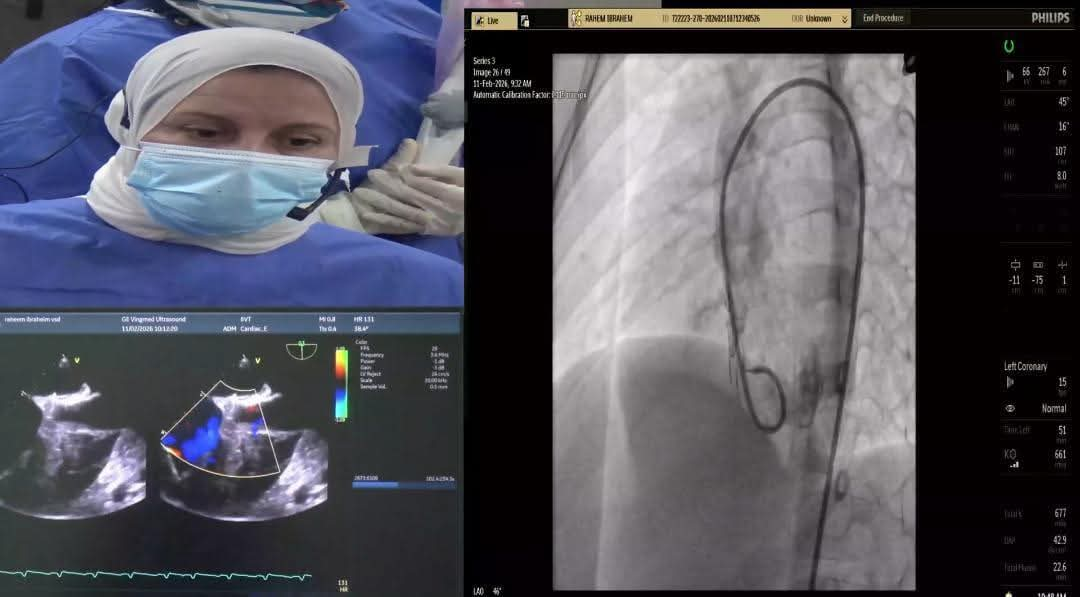

تأتي هذه الخطوة ضمن جهود المستشفيات لتقديم خدمات متطورة للأطفال المصابين بعيوب قلبية خلقية دون الحاجة لنقلهم لمراكز خارج المحافظة مما يقلل من أعباء الانتظار على الأسر ويمنح المرضى فرصة أفضل للحياة تم نقل العمليات مباشرة عبر بث حي خلال مؤتمر جمعية القلب المصرية السنوي مما أتاح للأطباء متابعة العمليات بدقة.

شملت الحالة الأولى طفلًا يبلغ من العمر خمس سنوات من محافظة كفر الشيخ يعاني من تضخم بعضلة القلب بسبب ثقب بين البطينين وتم غلق الثقب بنجاح باستخدام القسطرة التداخلية أما الحالة الثانية فكانت لشاب يبلغ 16 عامًا من محافظة الغربية يعاني من آثار جلطة سابقة وتم غلق ثقب خلقي بين الأذينين ليخرج الطفلان في حالة مستقرة ونتيجة مثالية.

شارك في العملية فريق طبي متكامل من أساتذة القلب والتخدير والعناية المركزة بالإضافة إلى تمريض المستشفى وفنيي الأشعة مما يعكس مستوى الخبرة والكفاءة التي وصلت إليها مستشفيات جامعة طنطا في التعامل مع أصعب الحالات الطبية للأطفال.